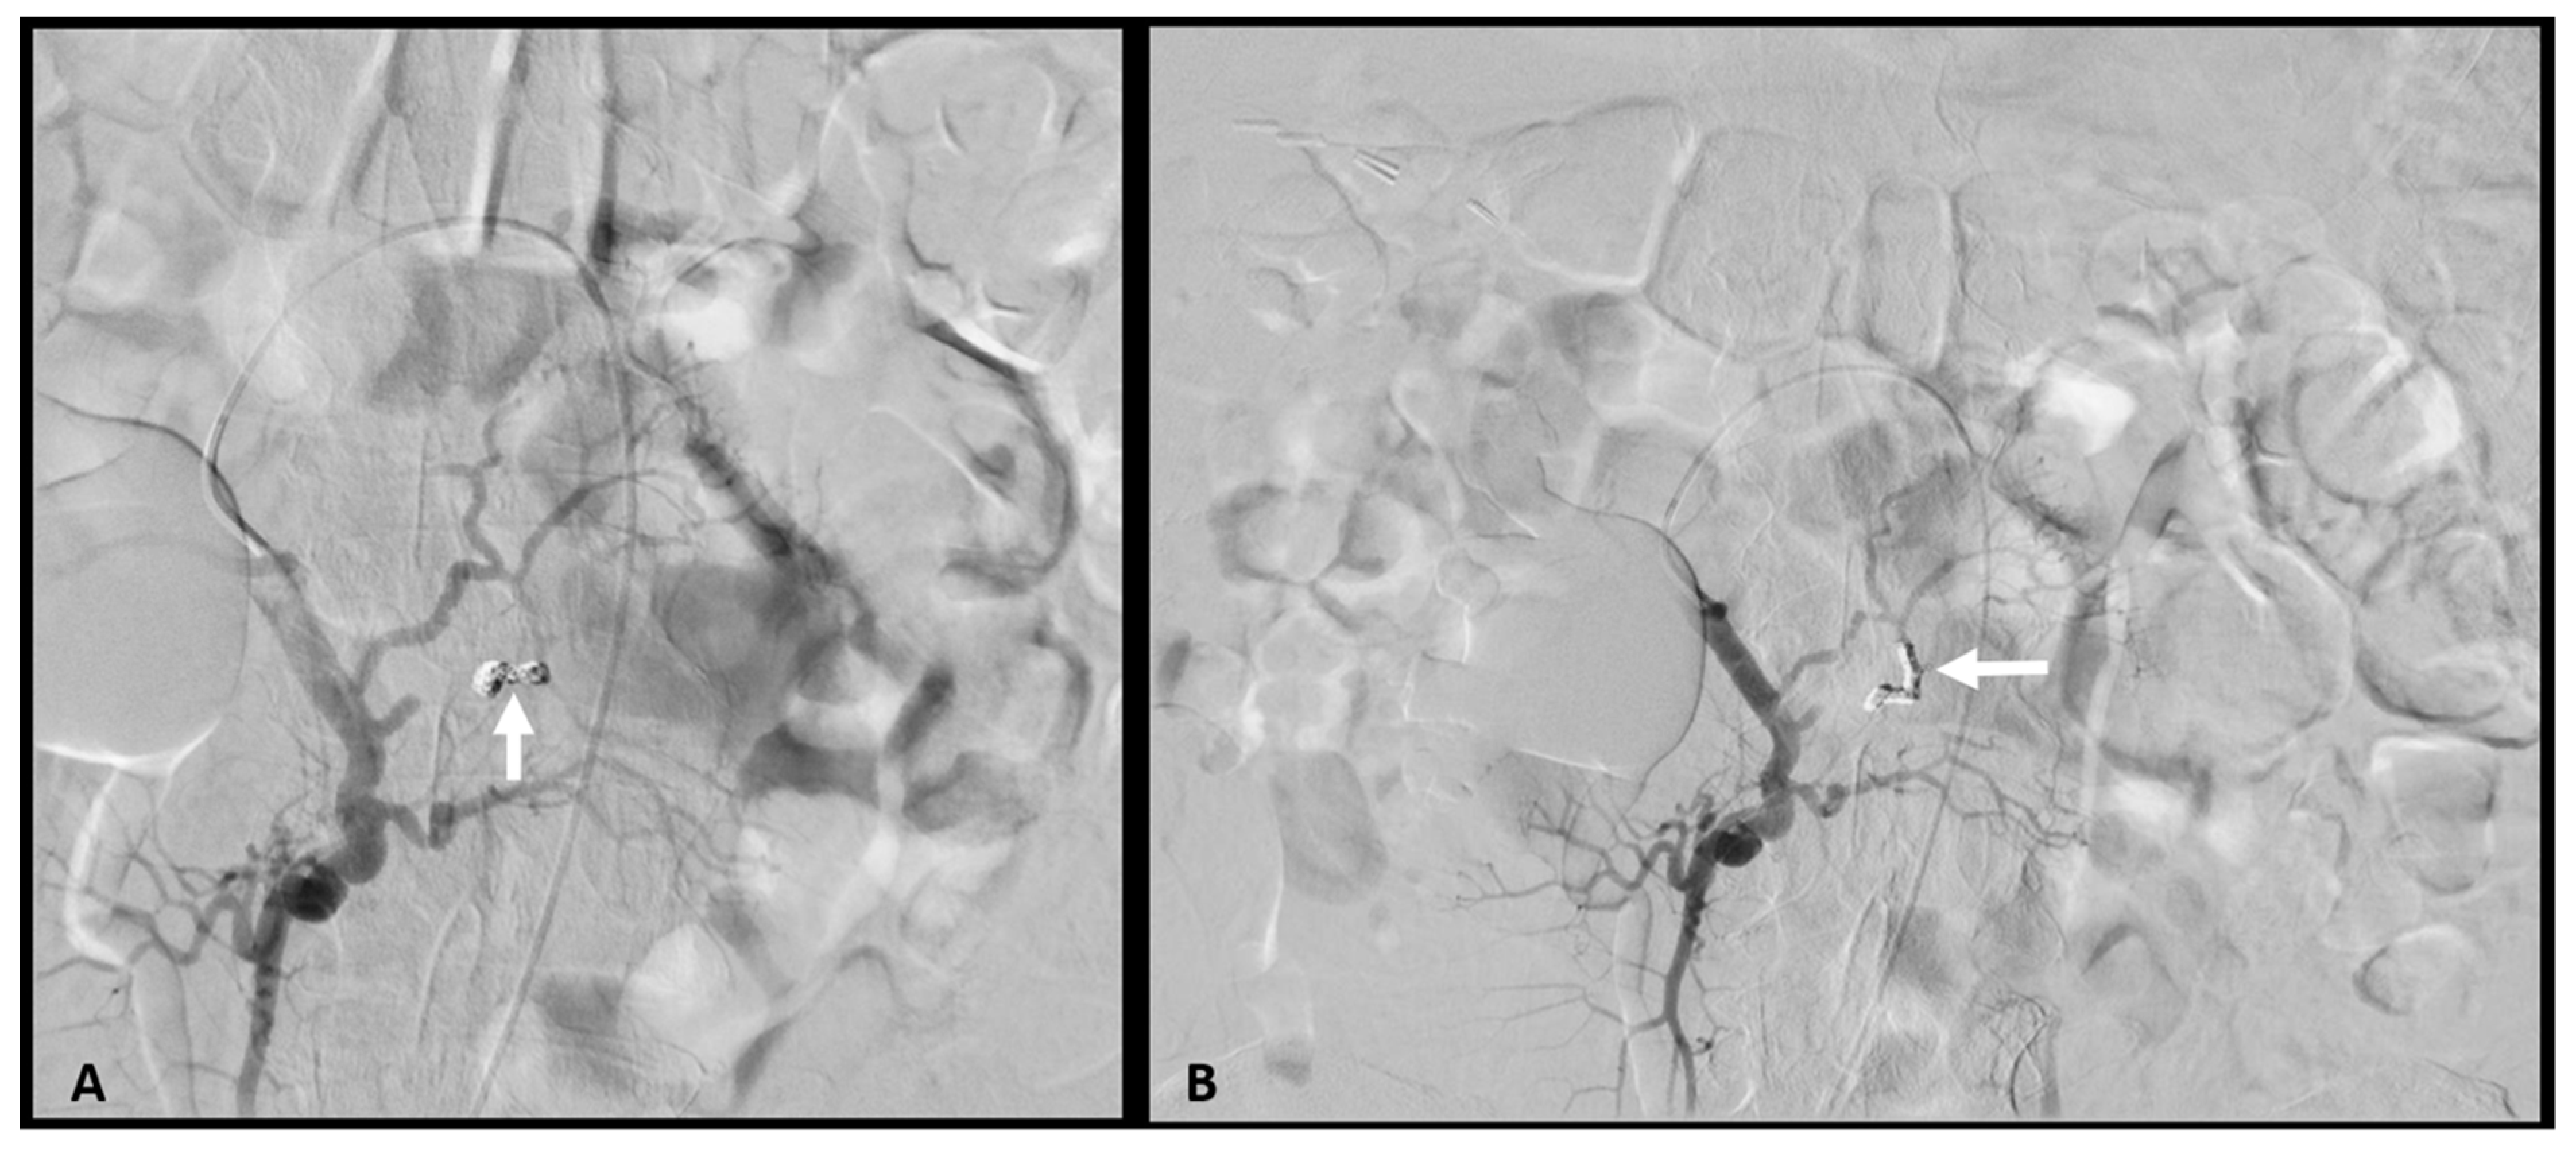

2. Case Report